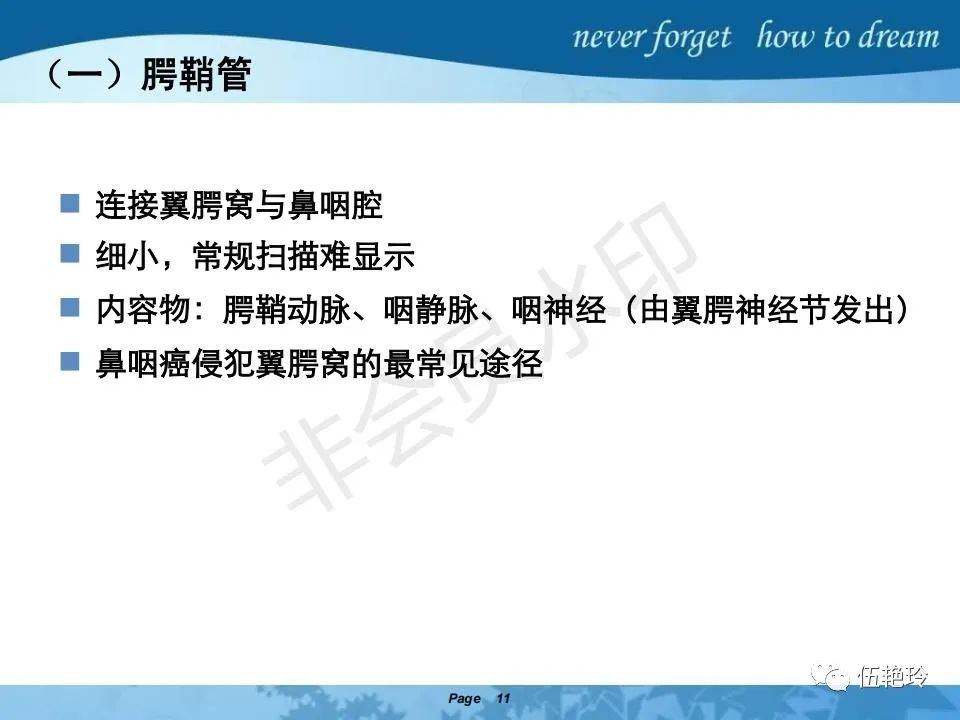

翼腭窝的解剖结构与鼻咽癌侵犯